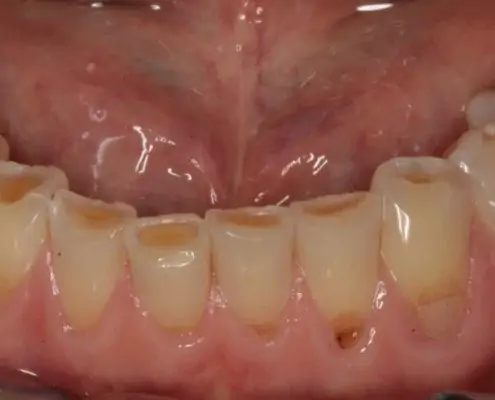

AvantAprès

Identifier les signes d’érosion dentaire

Les érosions dentaires peuvent être détectées lors d’un examen dentaire ou d’un détartrage. Des dents jaunies, une sensibilité accrue aux températures chaudes ou froides, ou des douleurs dentaires peuvent être des signes d’érosion dentaire.

Lorsque l’érosion est plus sévère il peut être indiqué d’effectuer un traitement de restauration  complète qui permet de rétablir l’esthétique et la fonction de mastication de vos dents.